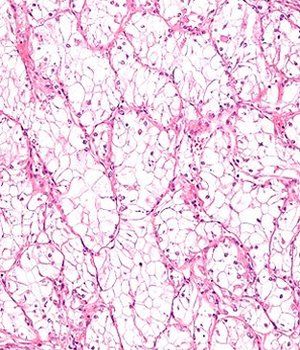

Intermediate magnification micrograph of a clear cell renal cell carcinoma; source: Nephron, Wikimedia Commons